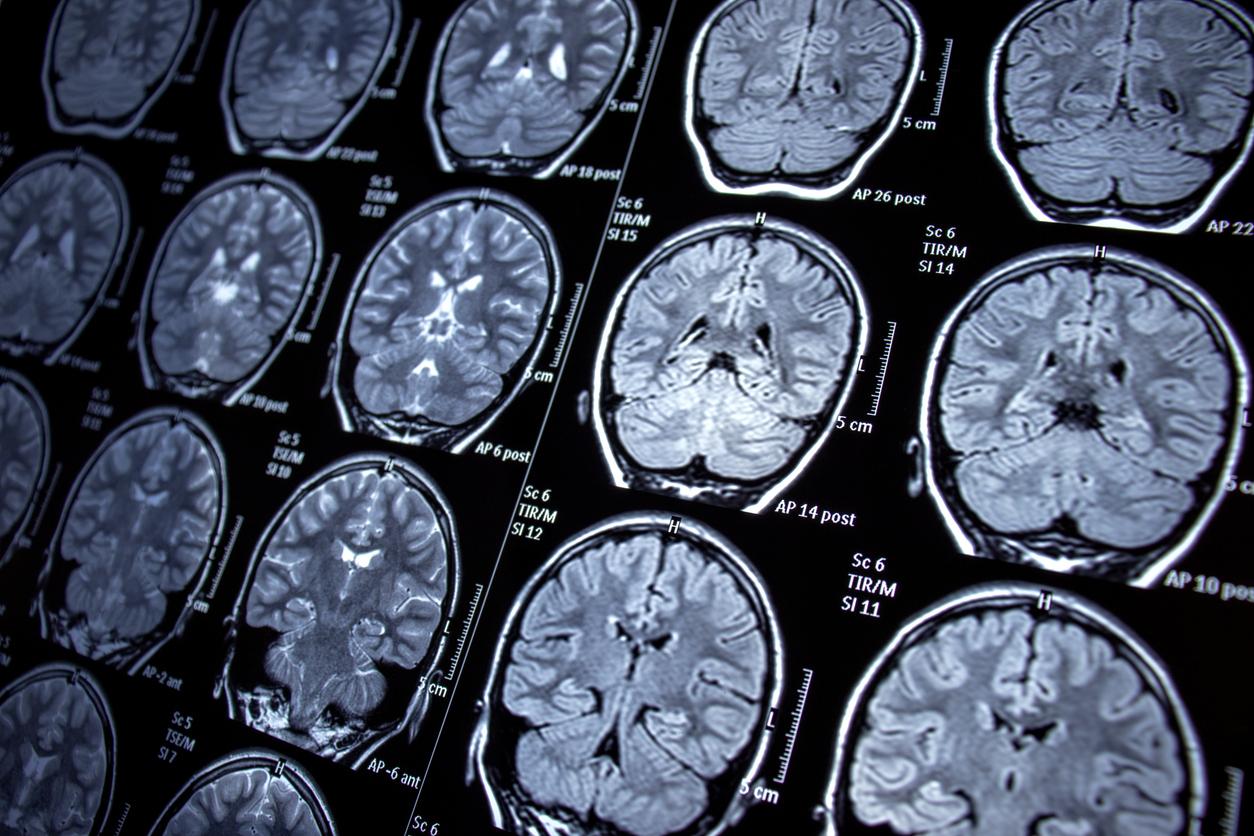

Ils nous servent quotidiennement et pourtant, jusqu’à présent, on ne les connaissait pas : les neurones ovoïdes. Selon une nouvelle étude, publiée dans la revue Nature Communications, ce sont ces neurones qui permettent au cerveau de mémoriser les objets. "La mémoire qui permet de reconnaître les objets est au cœur de notre identité et de la façon dont nous interagissons avec le monde, indique le Dr Mark Cembrowski, auteur principal de l’étude, dans un communiqué. Savoir si un objet est familier ou nouveau peut tout déterminer, de la survie au fonctionnement quotidien, et a d’énormes implications pour les maladies et troubles liés à la mémoire”.

À force de voir le nouvel objet, les neurones ovoïdes cessaient de réagir. Cela signifie qu’ils étaient actifs dans la phase de mémorisation mais que, par la suite, ils n'intervenaient plus dans la reconnaissance des objets. "D’un point de vue de neurosciences fondamentales, cela transforme réellement notre compréhension du fonctionnement de la mémoire, souligne le Dr Mark Cembrowski. (...) D’autres types de neurones, qui n’ont pas été découverts, pourraient donc exister dans le cerveau, chacun ayant des rôles spécialisés dans l’apprentissage, la mémoire et la cognition. Cela ouvre un monde de possibilités qui remodellerait complètement la façon dont nous abordons et traitons la santé et les maladies du cerveau”.

Forts de cette découverte, les chercheurs étudient désormais le potentiel rôle des neurones ovoïdes dans certaines maladies neurologiques comme Alzheimer ou l’épilepsie. "La mémoire de reconnaissance est l'une des caractéristiques de la maladie d'Alzheimer : vous oubliez ce que sont les clés ou la photo d'une personne que vous aimez, explique Adrienne Kinman. Et si nous pouvions manipuler ces cellules pour empêcher ou inverser ce phénomène ?”. Un espoir pour de nombreux patients. Pour rappel, actuellement, plus de 55 millions de personnes sont atteintes de démence dans le monde, selon l’Organisation mondiale de la Santé (OMS), dont la maladie d’Alzheimer serait à l’origine de 60 à 70 % des cas.